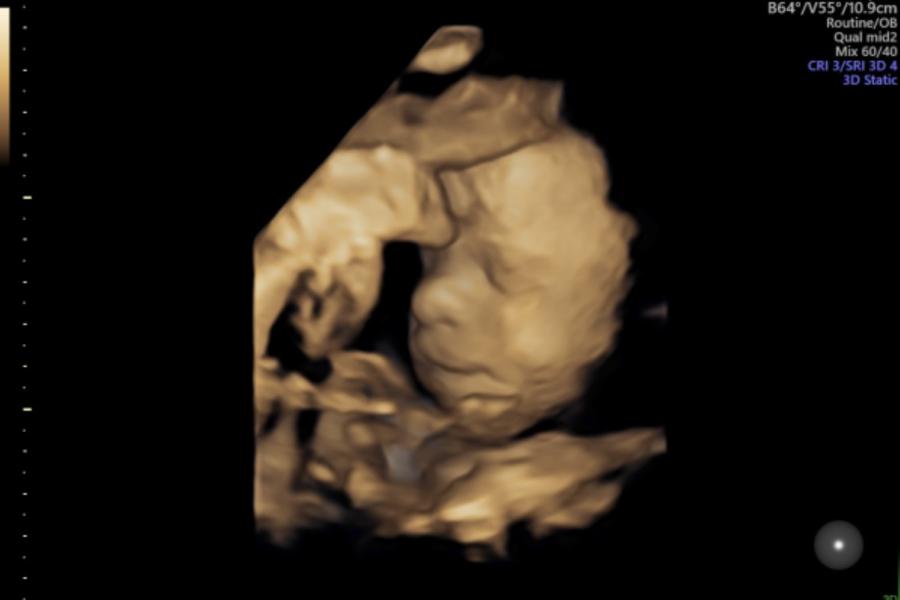

Ну копия папка!

Сынуля🙏🏻❤️